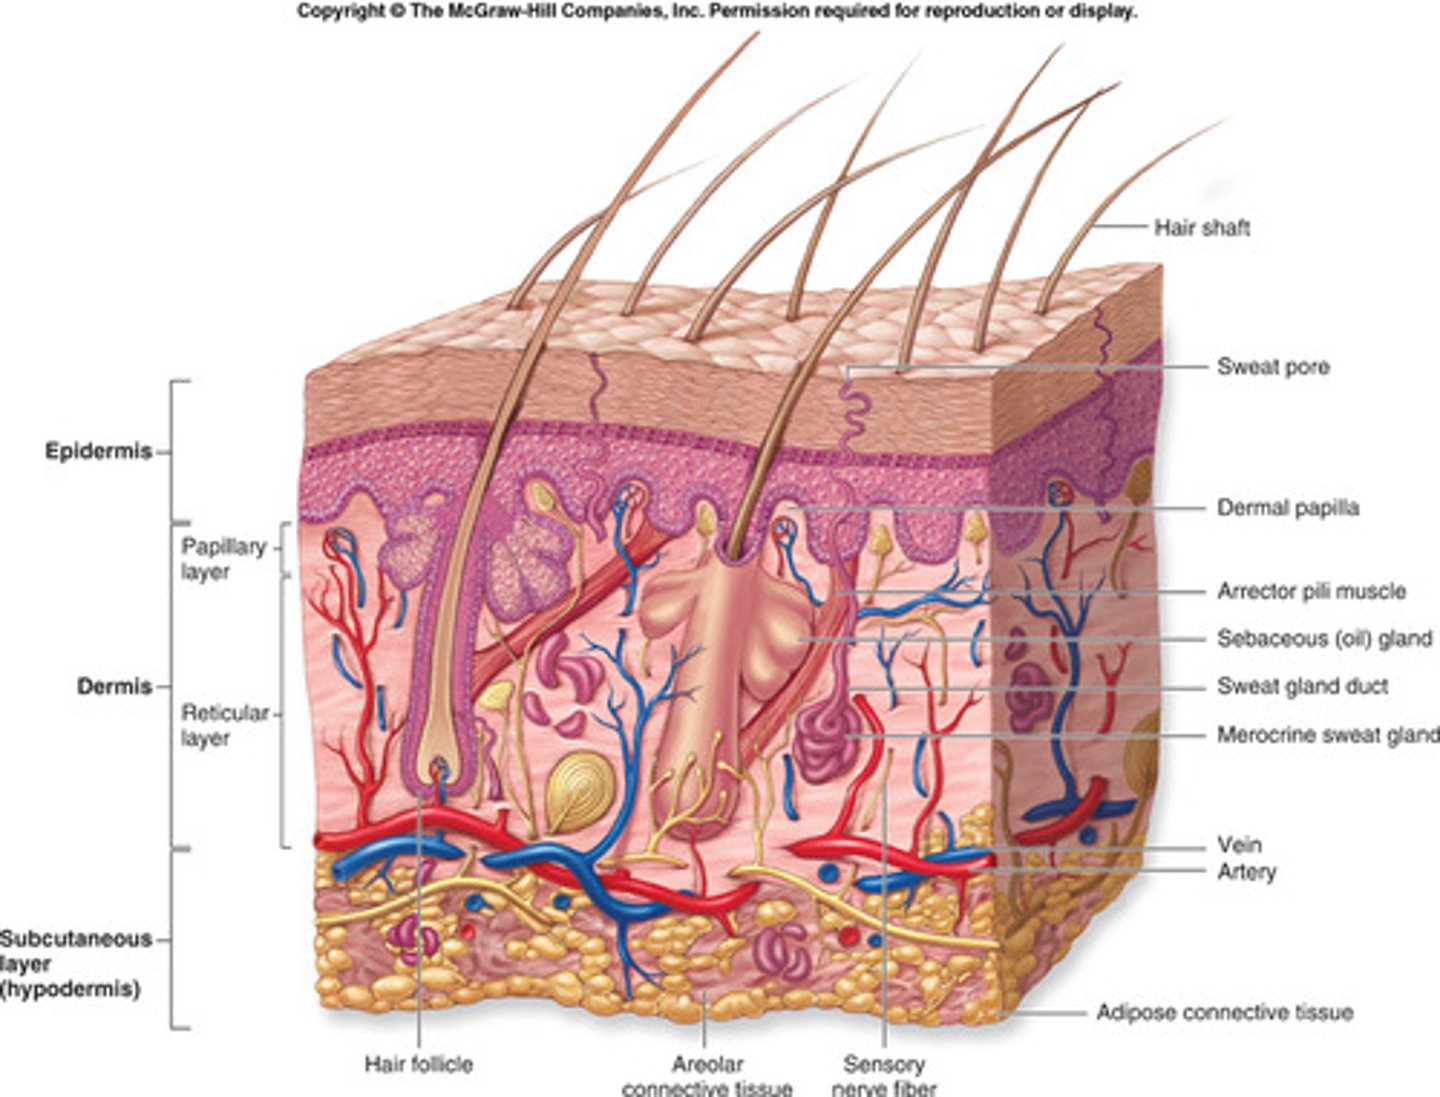

What is the integumentary system?

consists of skin, mucous membranes, hair & nails. This system also serves as a barrier to pathogens & helps regulate body temperature.